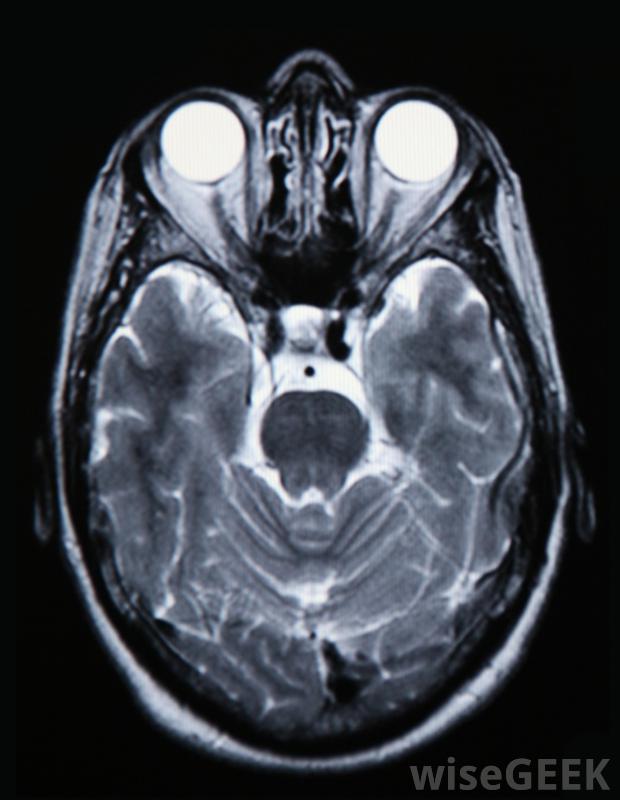

腦瘤化療的利與弊因癌癥的分期和腫瘤的類型而不同,其益處可能包括延長壽命或癌癥在治療后逐漸緩解,尤其是與其他治療方法相結合時,缺點包括化療不適合于許多類型的腦瘤,而且對于早期腫瘤也不是一種有效的治療方法。非癌性腫瘤通常不采用化療,尤其是當腫瘤沒有生長或引起任何嚴重問題時。腦部掃描將顯示腫瘤的位置,并幫助確定是否需要化療使用化學療法治療腦瘤不像其他潛在的治療方法那么普遍,原因有幾個。大腦有一種保護機制,可以將化學物質和其他毒素排除在外。這在大多數情況下是有益的,但它也能阻止化療藥物進入腦瘤,非癌性腫瘤通常從不接受化療,惡性腫瘤通常只有在進展后才使用藥物治療由于每個患者的身體反應不同,因此無法預測化療在對抗腦瘤方面的有效性有時,腦腫瘤的化療是有益的,特別是當與其他治療惡性腫瘤的藥物結合使用時,尤其如此。新的藥物正在開發中,專門針對某些類型的細胞。有些藥物可以在需要的地方直接注射,而另一些則是設計用來治療的阻止某些類型細胞或組織的生長。化療通常在輸液中心進行,在那里訓練有素的專業人員可以觀察不良反應用化療治療腦瘤的主要缺點是它通常不如其他替代療法有效。很多時候腫瘤必須通過手術切除。然后是放射治療,它的目的是幫助縮小任何現有的腫瘤組織和殺死癌細胞。有時化療是在這些治療完成后使用的,但并非所有類型的腫瘤都對藥物有反應。這意味著它們對某些腫瘤根本不是一個好的選擇,即使是在疾病的晚期大腦有一層保護膜,可以阻擋化學物質和毒素,從而阻止藥物進入腦瘤為了確定使用化療治療腦瘤是否是一個好的選擇,必須對大腦進行掃描,以確定腫瘤的位置和腫瘤的大小。可能要做一些測試來確定腫瘤是否是癌性的。如果不是,那么它們就很小,不會影響腦功能,醫生們可能會采取觀望的態度,仔細觀察腫瘤的生長情況。如果發現有癌變,可以通過手術和放療來切除或縮小腫瘤。而化療可以用來縮小腫瘤,許多腦腫瘤必須手術切除。在大多數情況下,良性腦腫瘤不需要化療。